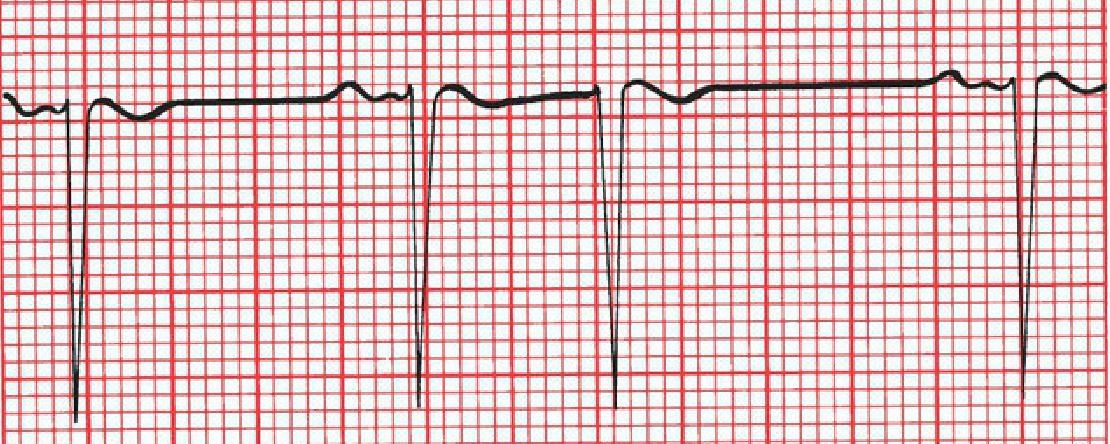

What’s the rate of the following EKG?

Every QRS complex is separated by five large squares (1 second). A rhythm occurring once every second occurs 60 times every minute.